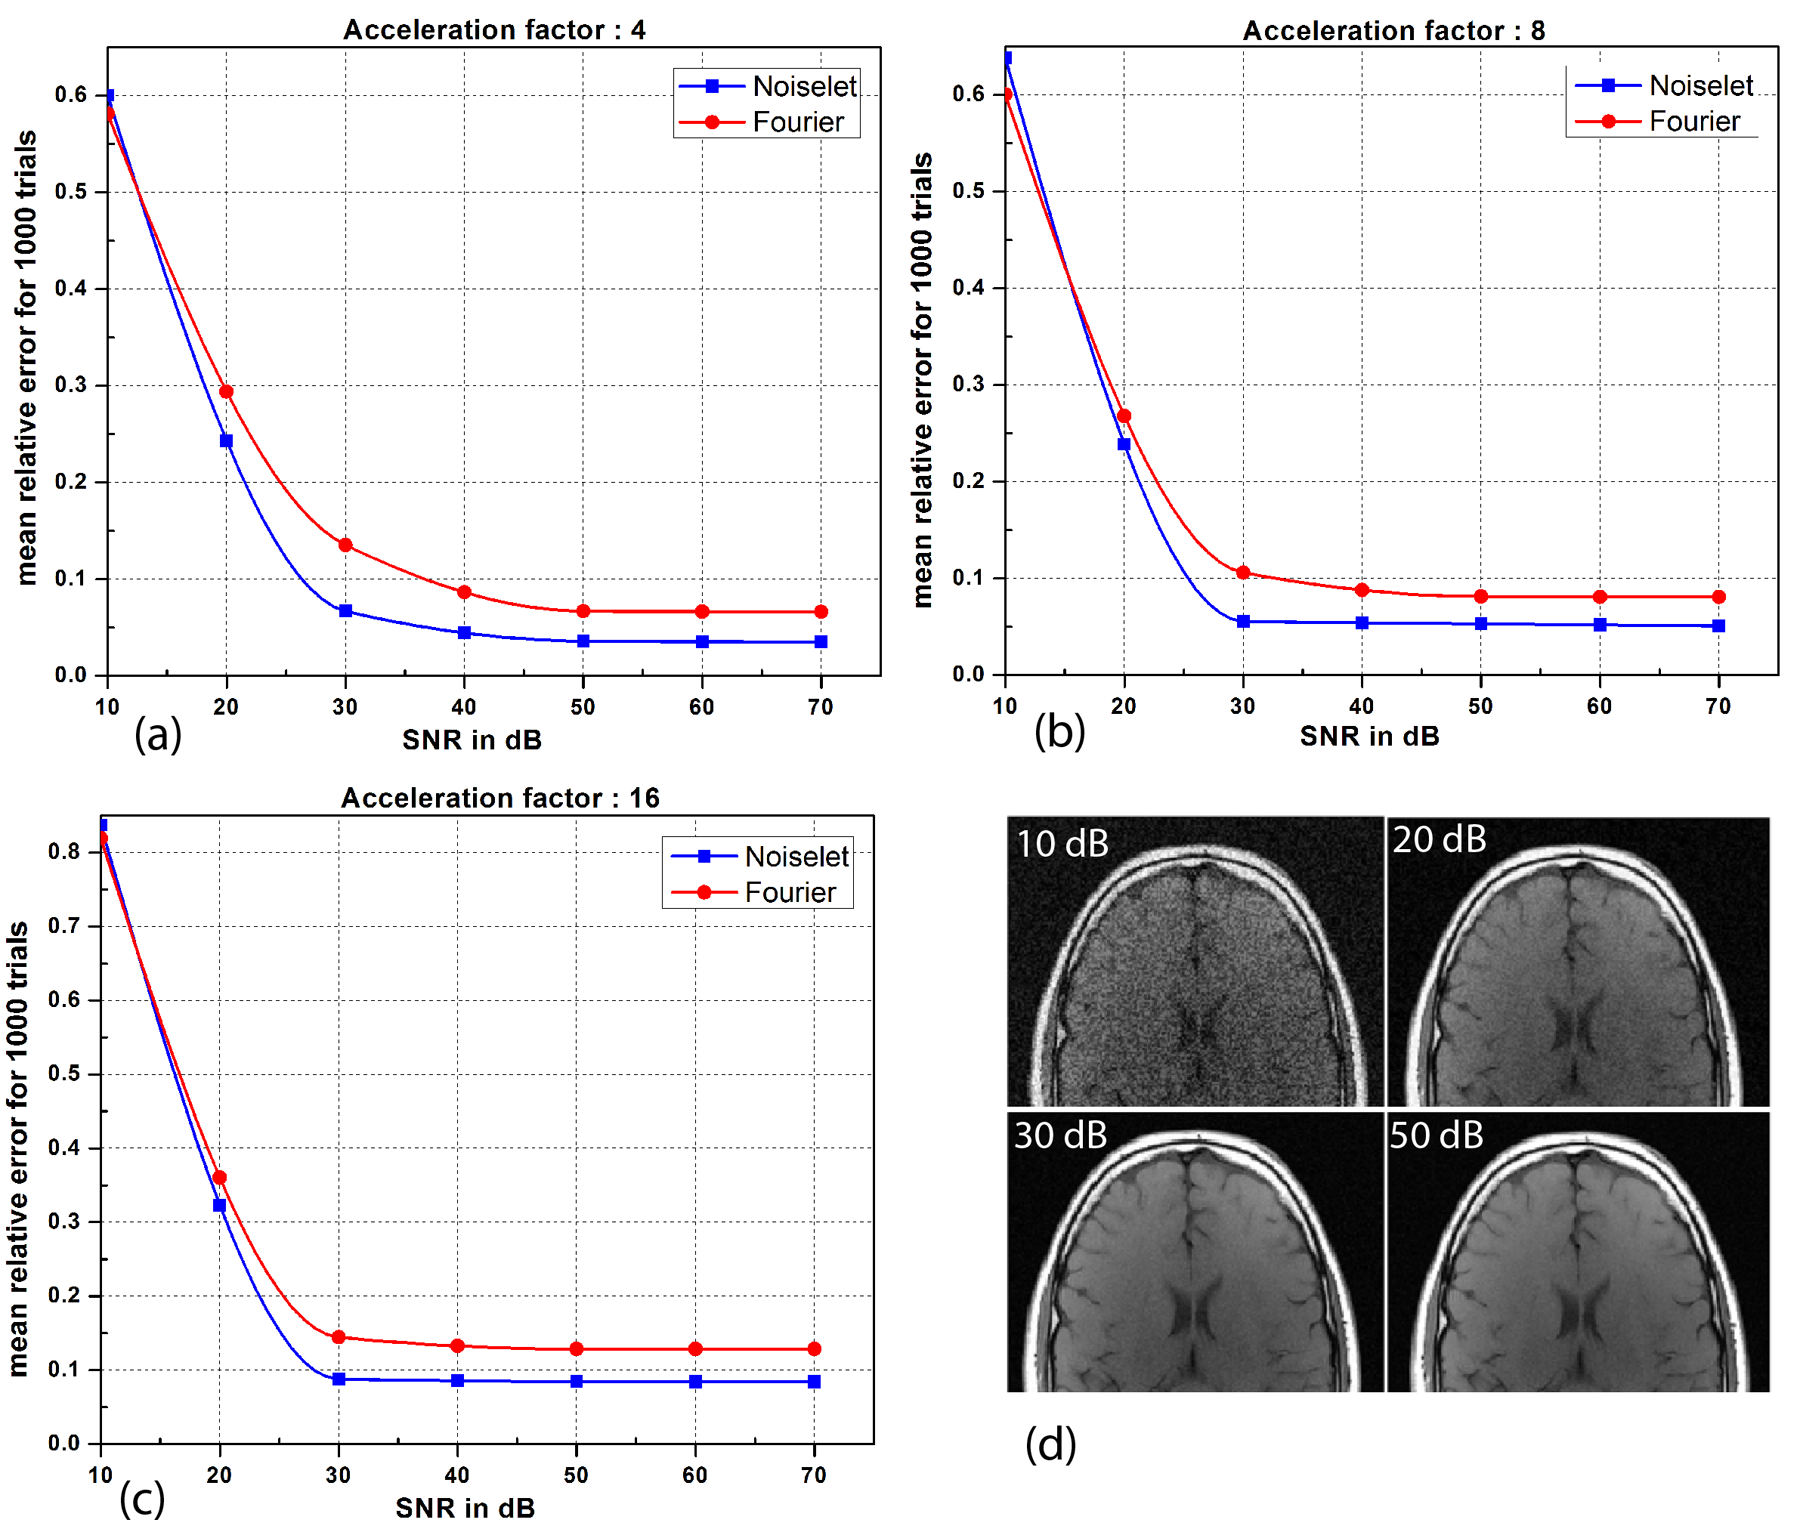

In practice, MR data always has some noise and the level of noise depends upon many factors including the FOV, resolution, type of imaging sequence, magnetic field inhomogeneity and RF inhomogeneity. Therefore, simulations were carried out to evaluate the performance of both the noiselet encoding and Fourier encoding schemes in the presence of variable levels of noise. Different levels of random Gaussian noise were added to the measured k-space data, and MCS-MRI reconstruction was performed for noiselet and Fourier encoding schemes. For every level of noise, 1000 simulations were performed and the mean of the relative error was calculated. Fig. 10 shows the mean relative error as a function of the Signal to Noise Ratio (SNR), demonstrating the comparative performance of noiselet encoding reconstructions and Fourier encoding reconstructions in the presence of noise. The plots demonstrate that noiselet encoding outperforms Fourier encoding for SNR above 20 dB for all acceleration factors, but does a poor job at SNR of 10 dB. However, as shown in the images in Fig. 10(d), only the images with SNR above 20 dB are adequate for diagnostic purposes. Thus, acquisitions with 10 dB SNR is not a viable scanner operation condition and the poor performance of noiselet encoding at 10 dB SNR is not a practical limitation. The poor performance of noiselet encoding at 10 dB SNR can be attributed to the fact that at extremely low SNR, most of the noiselet coefficients are severely corrupted by the noise since their magnitudes are approximately uniform. In contrast, the Fourier coefficients at the center of k-space have much larger magnitudes and hence are less affected by the noise at low SNR. These large magnitude coefficients are fully utilized in reconstruction because of the centralized variable density sampling scheme, hence Fourier encoding is less affected by the noise and performs better at low SNR.